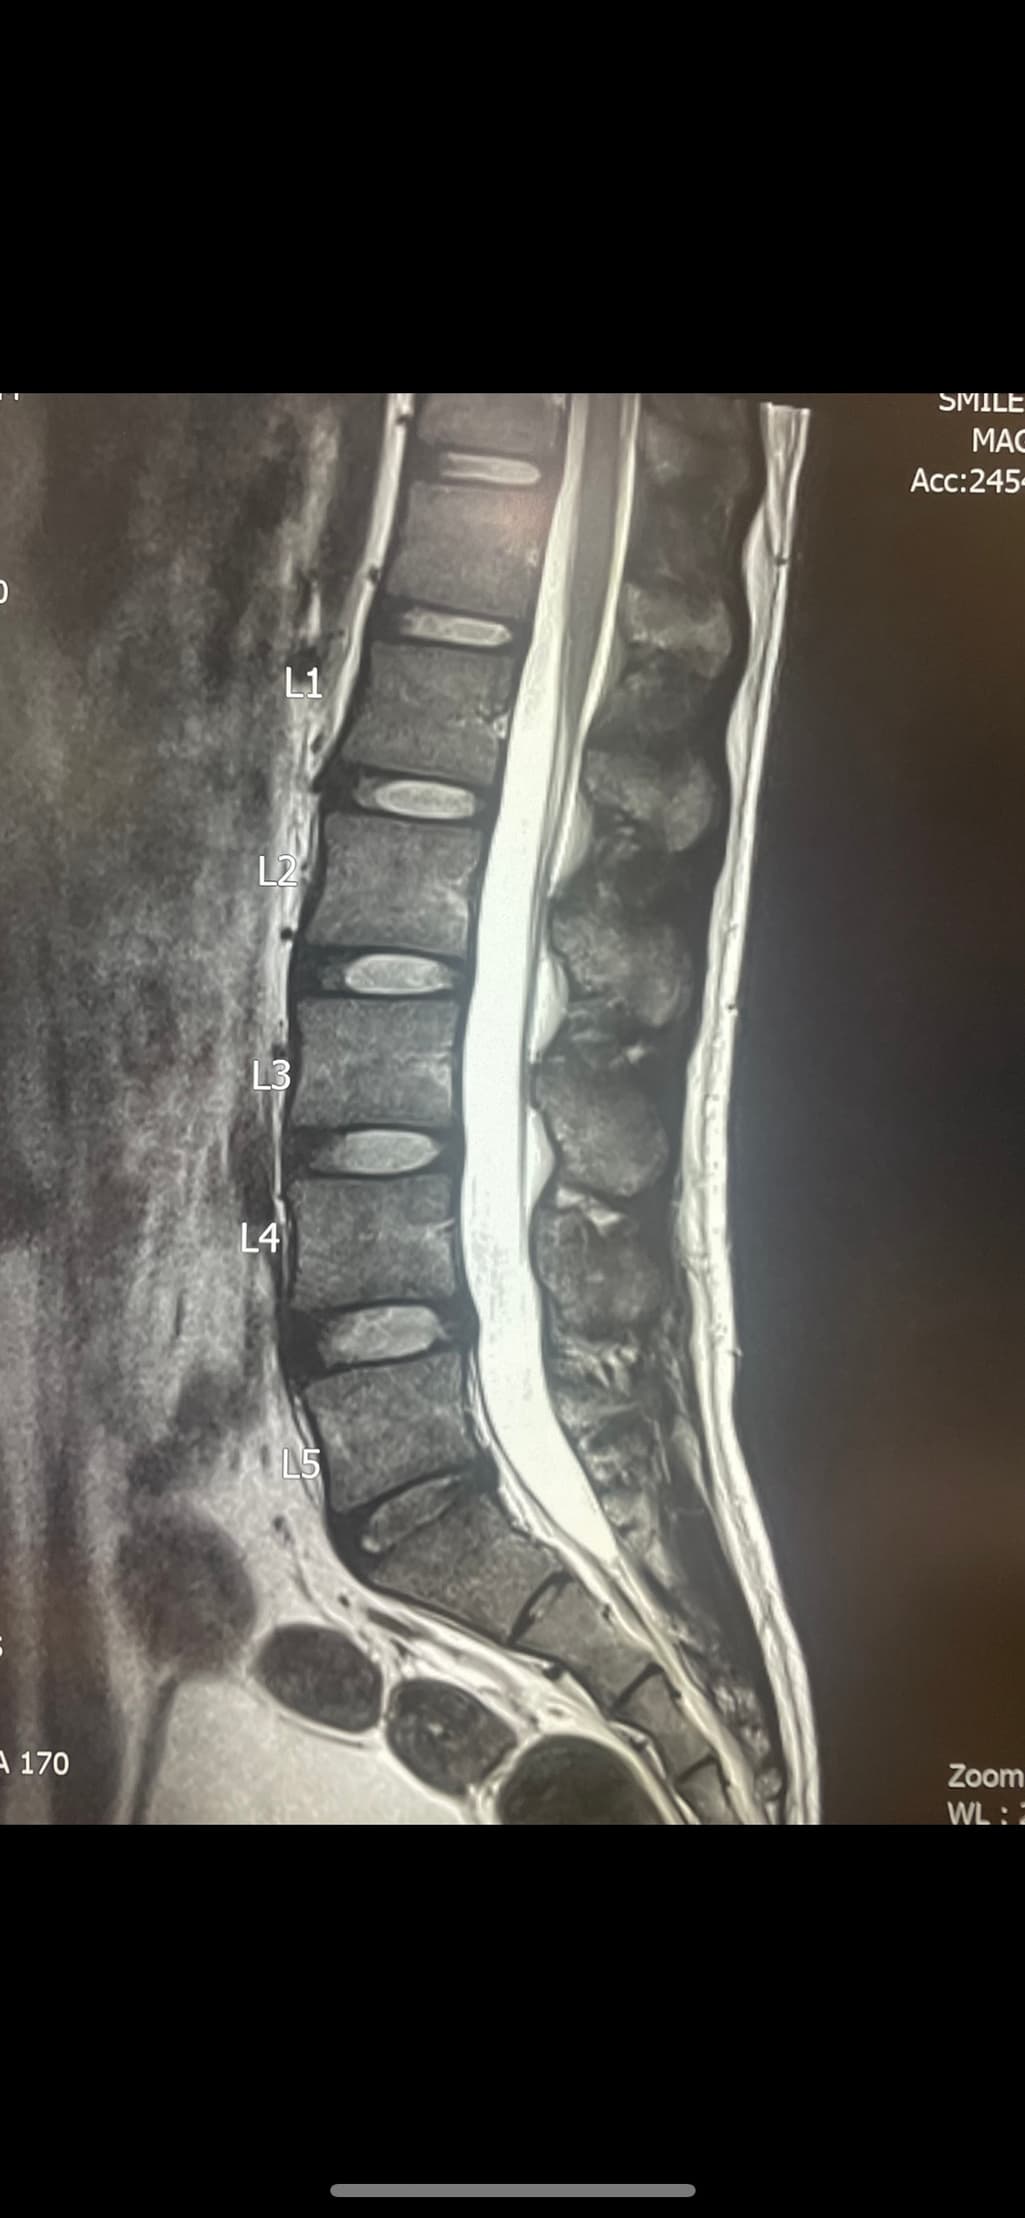

허리디스크 초기 판정을 받았습니다. 도움이되는 운동과 관리방법을 알려주세요. 지금어떤상태인지 초기는 완치 가능한지도 궁금합니다

• 1번 째 사진

허리 추간판의 약간의 돌출이 보이는 상태같습니다.

요추 5번 천추 1번 사이에 디스크내장증이 있어보입니다.

흔히 이야기하시는 디스크는 디스크탈출을 의미하는데 수핵이 탈출한 정도의 디스크는 아니고 디스크 섬유륜 일부층이 찢어지는 디스크내장증이 있는 상태로 보입니다.

디스크 내장증을 그냥 이해하기 쉬우시라고 디스크 초기라고 표현하시는 경우도 있겠습니다.